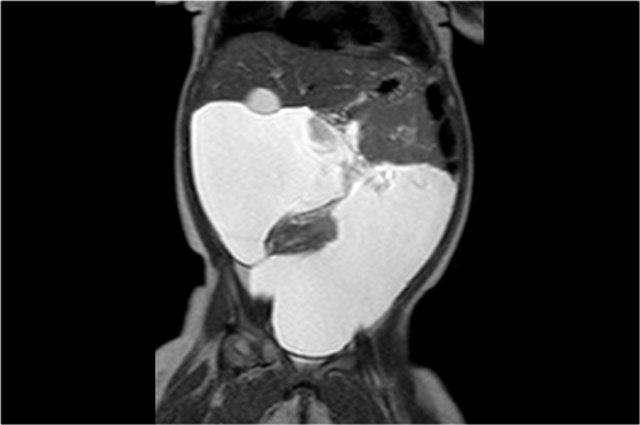

Bé trai một tuổi nhập viện vì bụng phình to.

Siêu âm phát hiện một tổn thương dạng nang kích thước lớn, trải dài từ gan xuống vùng chậu.

Ghi nhận có một số cặn lắng bên trong.

Ảnh MRI mặt phẳng coronal chuỗi xung T2W cho thấy rõ hơn mức độ lan rộng của tổn thương.

Trong phẫu thuật, tổn thương được xác định bám vào đại tràng lên, đại tràng này đã được cắt bỏ cùng với u nang bạch huyết.